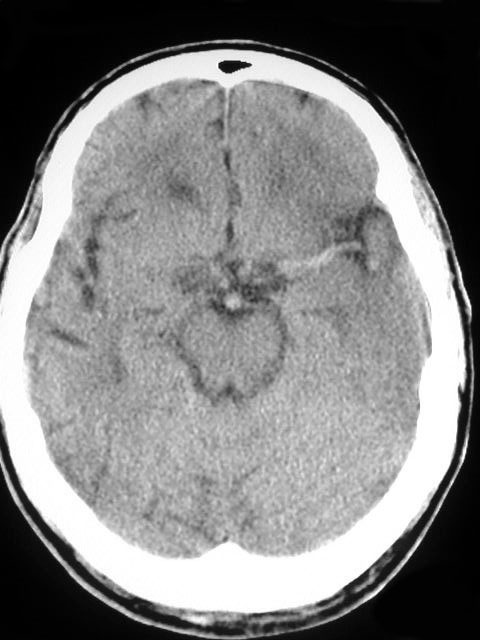

SIGNO DE LA PÉRDIDA DE SURCOS

Sutil pérdida de surcos en la convexidad derecha. En la TC de control se observa un infarto masivo en el territorio de la ACM derecha, con zonas hiperdensas por transformación hemorrágica.

La disminución del número y profundidad de los surcos de la convexidad cerebral es un signo poco específico, que se ha descrito como hallazgo precoz en el infarto isquémico cerebral. Está relacionado con el edema citotóxico que acompaña a la isquemia. También puede aparecer en el edema cerebral difuso y acompañando a lesiones expansivas cerebrales.